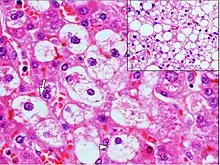

| Micrograph demonstrating marked (macrovesicular) steatosis in non-alcoholic fatty liver disease. Masson's trichrome stain. | |

Steatosis reflects an impairment of the normal processes of synthesis and elimination of triglyceride fat. Excess lipid accumulates in vesicles that displace the cytoplasm. When the vesicles are large enough to distort the nucleus, the condition is known as macrovesicular steatosis; otherwise, the condition is known as microvesicular steatosis. While not particularly detrimental to the cell in mild cases, large accumulations can disrupt cell constituents, and in severe cases the cell may even burst.

Histologically, steatosis is physically apparent as lipid within membrane bound liposomes of parenchymal cells.[2] When this tissue is fixed and stained to be better viewed under a microscope, the lipid is usually dissolved by the solvents used to prepare the sample. As such, samples prepared this way will appear to have empty holes (or vacuoles) within the cells where the lipid has been cleared. Special lipid stains, such as Sudan stains and osmium tetroxide are able to retain and show up lipid droplets, hence more conclusively indicating the presence of lipids. Other intracellular accumulations, such as water or glycogen, can also appear as clear vacuoles, therefore it becomes necessary to use stains to better determine what substance is accumulating.